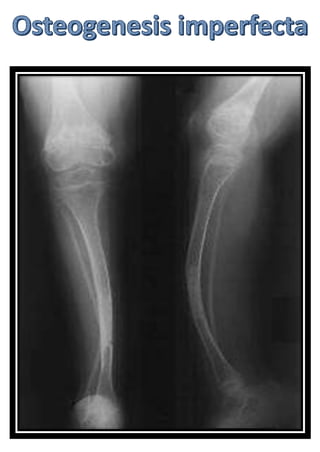

Head , neckand spine Basilar invagination Wormian bones Kyphoscoliosis Verebral compression fractures Codfish vertebrae Platyspondyly Chest Pectus excavatumor carinatum Pelvis Protrusio acetabuli Coxa vara

• 126.

General Severe osteoporosis Deformed bones Corticalthining Popcorn calcification: the metaphysis and epiphysis exhibit numerous scalloped radiolucent areas with sclerotic margins Zebra stripe sign : cyclic bisphosphonate treatment produces sclerotic growth recovery lines in the long bones. Formation of pseudoarthrosis at sites of healing fractures.